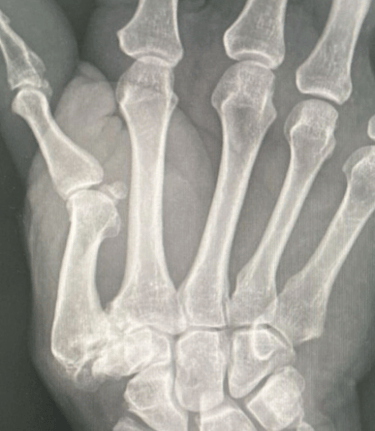

Fraturas e Luxações

Podem ocorrer na mão, punho ou antebraço por acidentes de trânsito, trabalho ou quedas. As mais comuns afetam os ossos da mão (metacarpos), dos dedos (falanges), antebraço (rádio e ulna) e punho (carpo).

O diagnóstico é feito com exames de imagem e avaliação clínica.

O tratamento pode ser conservador ou cirúrgico, conforme o tipo e a gravidade da lesão.